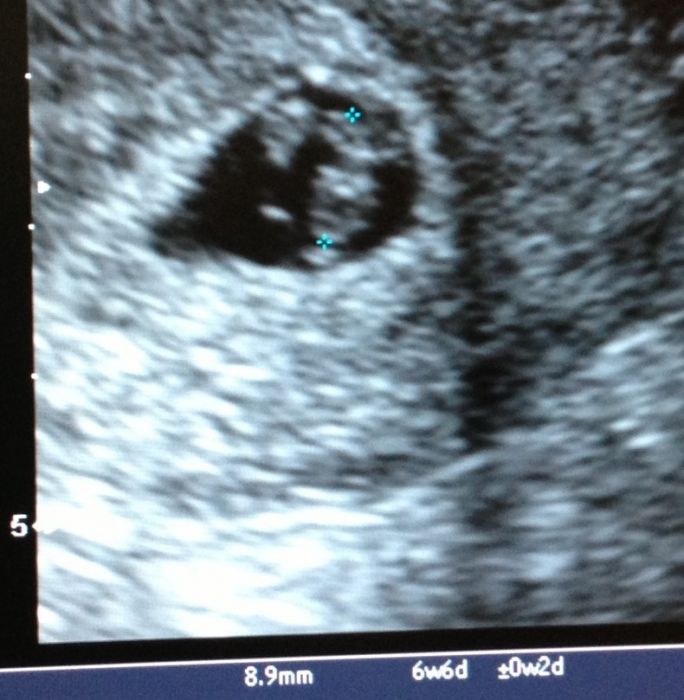

Ahoj holky a mimca, no my uz máme jednoho kloucka a další na ceste a stále je to přítel. Chci si svatbu užít či opít. No to je jedno, proste nechci aby se pak říkala musel si ji vzít. A popravdě kdyz se občas neshodnem, tak jsem pevne rozhodnuta, ze si ho nevemu :} o ruku me požádal 11.11.11 i s prstynkem. Pak 12.12.12 bez prstynku. A ted jsem zvědavá co bude dal :) :) :) holky tak ja vám vložím foto mého prvního ditka. Aby jste viděli jakou krasnou fotku jsem měla od svého Dr. a pak k porovnání i tu z pondělka. Fakt mega rozdíl. Jinak po 2 letech jsem se vyspala! Jen vím ze jsme lehla a pak probudila oči a říkám si to je světla. Maly spí a ze ja jsem k nemu v noci vstavat nemusela? :) no a hned zacal kmitat nozkama a křičet se zavřenýma očima hlady, ale az v 6 :))))

[569824] Luci,ja byla 6+3 a taky jsme meli 5mm a mam napsano,ze stari dle UZ je 6+4. Je to prumerna hodnota,bud uplne v klidu.:-D